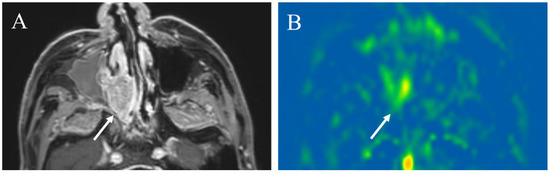

5.1.1. Inflammatory Lesions: Sialadenitis and Dacryoadenitis

5.1.2. Hypervascular Lesions

5.1.3. Salivary Gland Tumor Differentiation: Malignant Salivary Tumors, Pleomorphic Adenomas, and Warthin’s Tumors